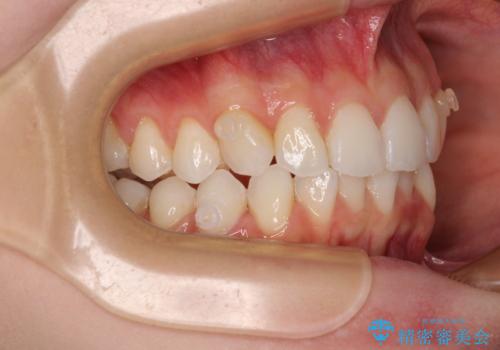

前歯のデコボコと深い咬み合わせ インビザラインできれいに改善

- 前歯のデコボコと下の前歯が隠れてしまう咬み合わせを気にして来院された患者様です。

インビザラインによる上下歯列の拡大と、IPR(歯と歯の間を削る)にるスペースの獲得により、口元のデコボコとディープバイトを改善することとしました。